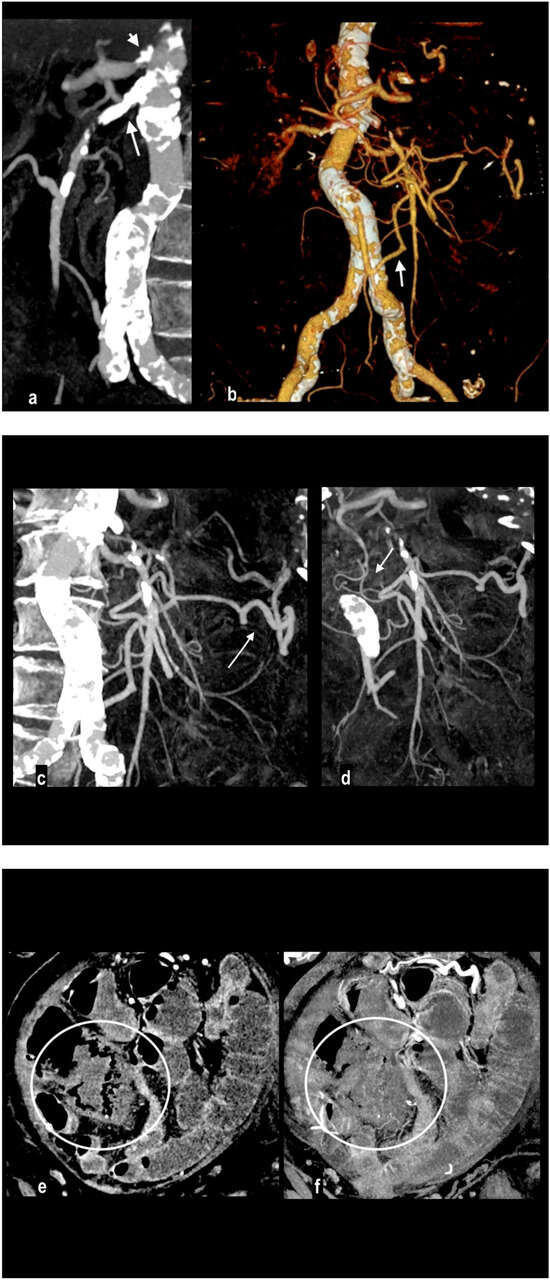

Figure 1.

Abdominal pain in a 91-year-old woman with diffuse calcified vascular atheromasia. MIP arterial reconstruction (a) showed calcified occlusion of the proximal SMA (arrow) and critical ostial occlusion of the celiac trunk (arrowhead). VR reconstruction (b) well depicted an ectasis mesenteric inferior artery and a dilated Riolan artery (arrow), that allowed the collateralization of the middle SMA and its branches. MIP reconstructions showed a large caliber of splenic flexure arteries ((c) arrow) and pancreatico-duodenal arteries ((d) arrow). However, a watershed territory (ileocecal junction) did not receive appropriate hematic flow and caecum necrosis developed, with hypoenhancing wall thickness and parietal pneumatosis (circle; (e) coronal MPR; (f) coronal MIP).